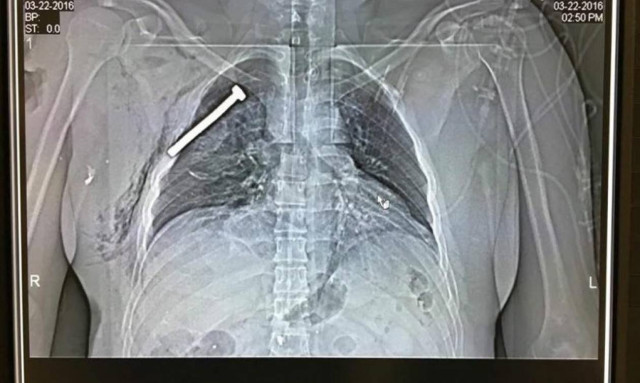

Σε αυτήν την κατεύθυνση η τουρκική αστυνομία έδωσε στη δημοσιότητα φωτογραφία του Μπακράουι από τη σύλληψη του τον περασμένο Ιούλιο.